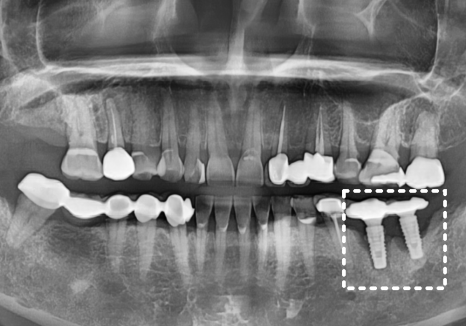

방사선 사진을 살펴보니,

임플란트 주변 뼈가 이미

상당히 소실되어 있는 상태....

CT 상에는 임플란트 뿌리의

약 2/3 정도의 뼈가 녹아,

뿌리 끝부분만 간신히 뼈에 매달려 있는 것을

확인할 수 있었어요.